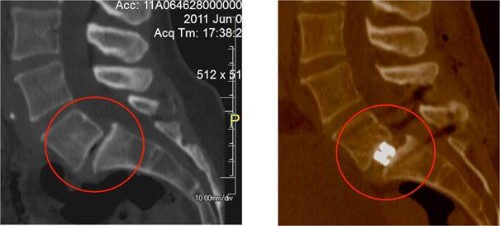

TAC postoperatori mostrant un disc L5/S1 molt col·lapsat (esquerra) i amb l’alçada

restaurada després inserció i expansió de l’implant expansible (dreta)